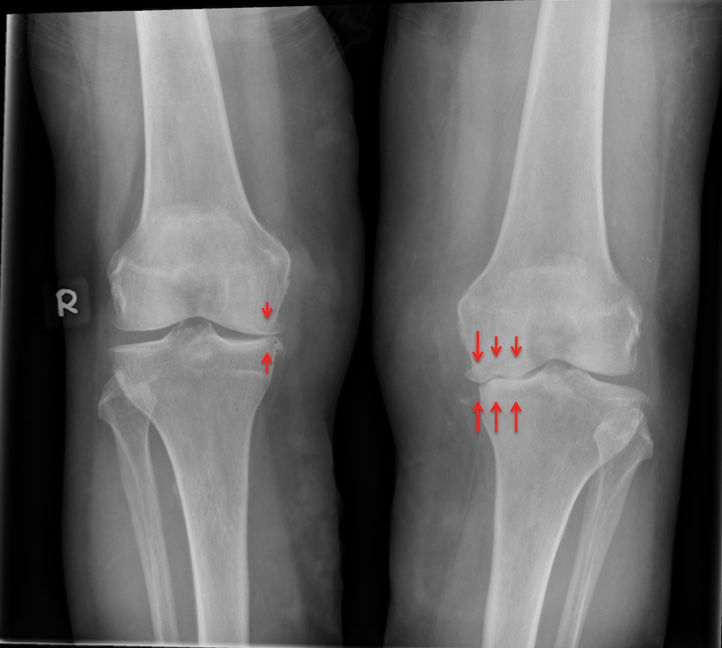

- Radiografia oferă imagini detaliate ale oaselor și poate evidenția îngustarea spațiului articular, modificări osoase și osteofite.

În această formă de artroză, cartilajul din articulația genunchiului se degradează treptat. Pe măsură ce se tocește, devine aspru și deteriorat, iar spațiul de protecție dintre oase se reduce. Acest lucru poate duce la frecarea os pe os și la apariția osteofitelor (ciocuri osoase).

Este o boală cronică care afectează mai multe articulații din corp, inclusiv genunchiul. Este simetrică, ceea ce înseamnă că afectează de obicei aceleași articulații pe ambele părți ale corpului.